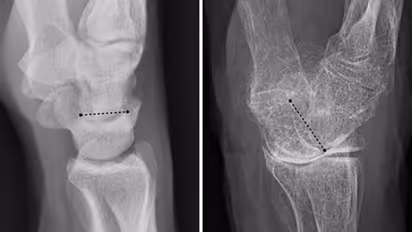

വളരെ പതുക്കെ അസ്ഥികൾക്കുണ്ടാകുന്ന ഈ വൈകല്യം എല്ലുകളുടെ തേയ്മാനത്തിനും ബലക്ഷയത്തിനും പൊട്ടലിനും കാരണമാകുമെന്നാണ് വിദഗ്ധർ പറയുന്നത്. പ്രായമാകുമ്പോൾ ചെറുതായി ഒന്ന് കാല് തെന്നിയാൽ പോലും വലിയ രീതിയിൽ എല്ലുകൾ പൊട്ടുന്നതിലേക്ക് നയിക്കുന്നത് ഓസ്റ്റിയോ പൊറോസിസാണ്.

പുരുഷന്മാരെക്കാൾ സ്ത്രീകളിലാണ് ഈ രോഗം കൂടുതലായി കണ്ട് വരുന്നത്. ആർത്തവ വിരാമത്തോടു കൂടി സ്ത്രീകളിലുണ്ടാകുന്ന ഹോർമോൺ വ്യതിയാനങ്ങളാണ് കാരണം. ഈസ്ട്രജൻ കുറയുന്നത് അസ്ഥിയുടെ കട്ടി കുറയാൻ കാരണമായി തീരുന്നു. സ്ത്രീകളിലെ ഇടുപ്പ്, കൈക്കുഴ, നട്ടെല്ല് എന്നീഭാഗങ്ങളിലെ വേദനയ്ക്കെല്ലാം ഓസ്റ്റിയോ പൊറോസിസ് കാരണമാകാം.